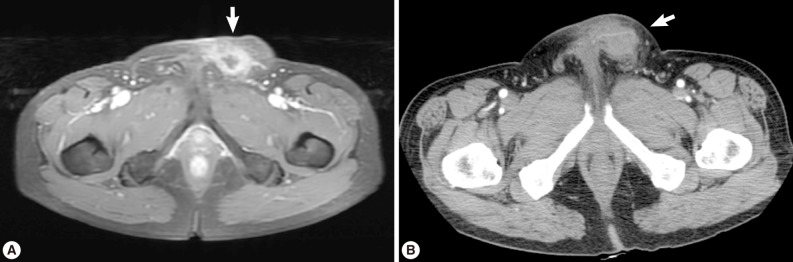

A 56-year old male visited our out-patient clinic for pancytopenia. Bone marrow biopsy and karyotype analysis showed myelodysplastic feature with 14% blast count and normal karyotype, indicating MDS, refractory anemia with excessive blast. He received 4 cycles of decitabine treatment during searching for matched unrelated donor, and partial response was shown. Allogeneic peripheral HSCT with myeloablative conditioning regimen consisting of busulphan and cyclophosphamide was performed from a HLA full-matched unrelated donor. However, at day 5 post-HSCT, 5 cm-sized hard and movable mass in the left scrotum and multiple palpable lymph nodes was detected at the left inguinal area. Pelvic magnetic resonance imaging and computed tomography were done and it was suspected initially as a myeloid sarcoma in the subcutaneous fat layer of the left scrotum and pathologic lymphadenopathy at the left inguinal area (Fig. 1). In order to confirm the diagnosis, gun biopsy was done on the left scrotal mass to avoid bleeding due to thrombocytopenia after HSCT. The result of the gun biopsy was inflamation of fibrovascular soft tissues with extensive interstitial eosinophilic infiltrations without evidence of malignancy. Persistent peripheral eosinophilia was also developed after HSCT. Subsequently, IgG antibody tests for paragonimiasis, cysticercosis, sparganosis, and clonorchiasis were done, and the results were positive for sparganosis and negative for all others. We re-evaluated the patient's past history and found out that he had swam in the river and ate raw fish, cow liver, and pork meat frequently when he was young. For a next step, excision biopsy was done as an approach for therapeutic diagnosis after recovery of thrombocytopenia. The cut surface of the biopsied specimen showed a cyst filled with whitish and myxoid tissues, measuring 2.0×0.6 cm (Fig. 2). The biopsy result was severe acute and chronic inflammation and fibrosis with a sparganum worm (Fig. 3). He was discharged after complete wound healing and stabilization of the post-HSCT condition.

A grayish soft tissue cut surface showing a cyst filled with whitish myxoid tissues of the plerocercoid larva (sparganum).